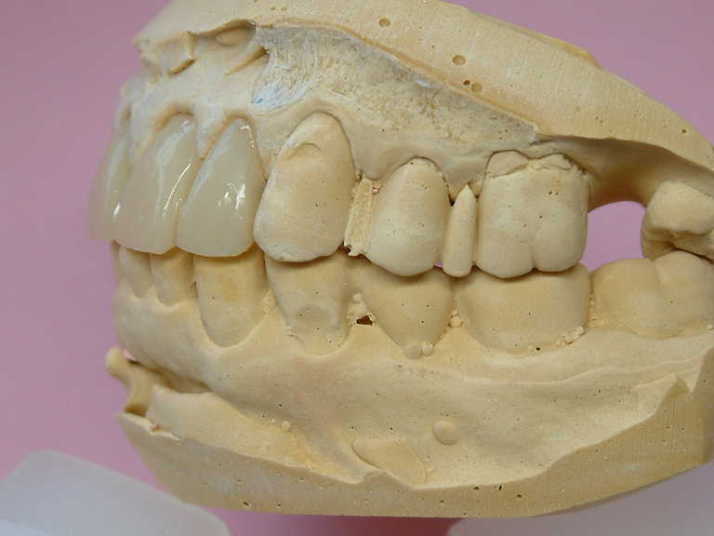

2-2 MB連結冠

※前突した形態と色を修正したケース

患者さんの希望として

☆出歯を直して内側に入れて欲しい

☆綺麗な歯にして欲しい

医師からの疑問として

☆1.1の間の小ダミーを取り除いて審美的に

美しい歯を作り上げることができるのか?

技工士からの回答として

☆下顎前歯の切端を削って頂ければ

2〜2を内側に入れて審美的にも納得して

頂ける補綴物が出来ると思われます。

☆テックにて患者さんが満足されるか確認してから

最終補綴物に移行しましょう

☆2.2の歯の幅を広げ、1.1の幅を狭くし

全体のバランスを取り作りたいと思います

☆1〜1の間の歯間空隙部分が不自然にならない

よう歯肉模型にて確認しながら製作します |